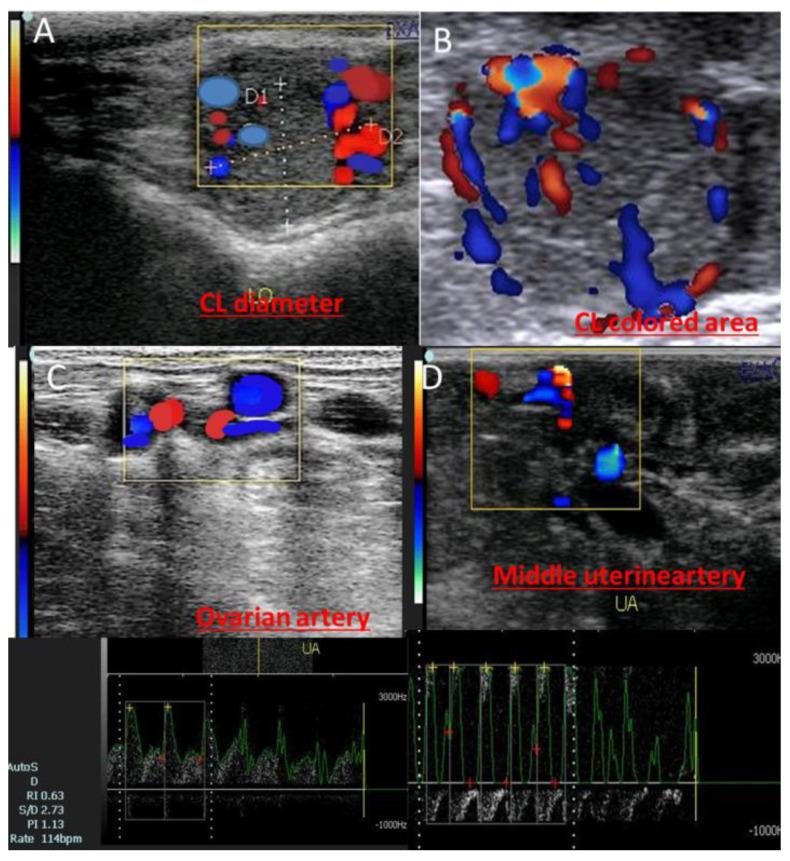

This current study examined the ovarian (OA) and middle uterine arteries (MUA) blood flow under heat stress conditions regarding hormonal status (progesterone (P4), estradiol (E2), and nitric oxide metabolites (NOMs) assays). Eighteen pluriparous cows were examined, with twelve only being subjected to the natural mating as the other six animals were not bred. Pregnancy diagnosis was confirmed at day 30 by embryonic heartbeat and CL graviditatis ( = 6; pregnant), but some animals ( = 6) showed early embryonic death (EED), with the presence of control cows ( = 6). In the pregnant group, luteal diameter (cm) increased after mating, while in the pregnancy loss group it increased ( < 0.05) until reaching day 38 (1.41 ± 0.03), then decreased again. Luteal vascularity was declined in cows with EED after day 36 ( < 0.05) and reached its lowest level at day 50. P4 levels elevated in cows with EED until day 36 (13.64 ± 0.11) then declined. Both ipsilateral OA and MUA Doppler indices were declined in both groups except in cows who suffered from EED; both were elevated from day 38 until day 50 after mating. Ipsilateral peak systolic point (PSV cm/sec) of OA and MUA was elevated in both groups ( < 0.05), but in cows with EED this parameter was declined. E2 and NOMs levels were declined in cows with EED from day 40 and day 38 after mating ( < 0.05), respectively. This study provided novel data on the relations among the luteal diameter, E2, P4, and NOM levels, and luteal hemodynamics that predicts the amount of blood supply, which acts as a sensitive parameter to detect the alterations in luteal function during the first 50 days after mating.

本研究在热应激条件下,就激素状态(孕酮(P4)、雌二醇(E2)和一氧化氮代谢产物(NOMs)检测)对卵巢动脉(OA)和子宫中动脉(MUA)的血流情况进行了检查。对18头经产母牛进行了检查,其中12头仅进行自然交配,另外6头未进行配种。在第30天通过胚胎心跳和妊娠黄体(CL graviditatis)确认妊娠诊断(=6;妊娠),但一些动物(=6)出现早期胚胎死亡(EED),同时设有对照母牛(=6)。在妊娠组中,配种后黄体直径(cm)增加,而在妊娠丢失组中,黄体直径增加(<0.05),直至第38天达到(1.41±0.03),然后再次下降。在第36天后,发生EED的母牛黄体血管化程度下降(<0.05),并在第50天达到最低水平。发生EED的母牛P4水平在第36天之前升高(13.64±0.11),然后下降。除了发生EED的母牛外,两组的同侧OA和MUA多普勒指数均下降;配种后从第38天到第50天,这两个指数均升高。两组中OA和MUA的同侧收缩期峰值点(PSV cm/秒)均升高(<0.05),但发生EED的母牛该参数下降。发生EED的母牛中,E2和NOMs水平分别在配种后第40天和第38天下降(<0.05)。本研究提供了关于黄体直径、E2、P4和NOM水平以及黄体血流动力学之间关系的新数据,黄体血流动力学可预测血液供应量,是检测配种后前50天黄体功能变化的敏感参数。